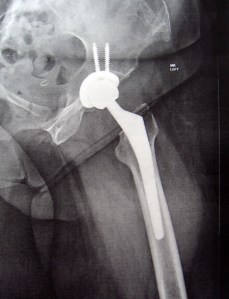

I saw my doctor, Bryan Springer, MD of OrthoCarolina, exactly one month after my surgery. The first thing he said was when he did the surgery my hip looked pretty bad in there, then he showed me my x-ray of my new hip, and said I was doing great! I go back to see him in 3 months! Woo Hoo! I did request to go to further physical therapy since I didn’t get to finish my PT at home and he was all for it. Unfortunately, I haven’t been able to start it yet. I’ll be doing Aquatic Therapy and the place I went before have drastically cut their hours so I’ll be going to a different place. I’m a little nervous because the other place was very quiet and I could easily hear my therapist. I don’t know how the new place will be, I have a LOT of trouble with my hearing so if it is the slightest bit noisy in there I may have a lot of difficulty.